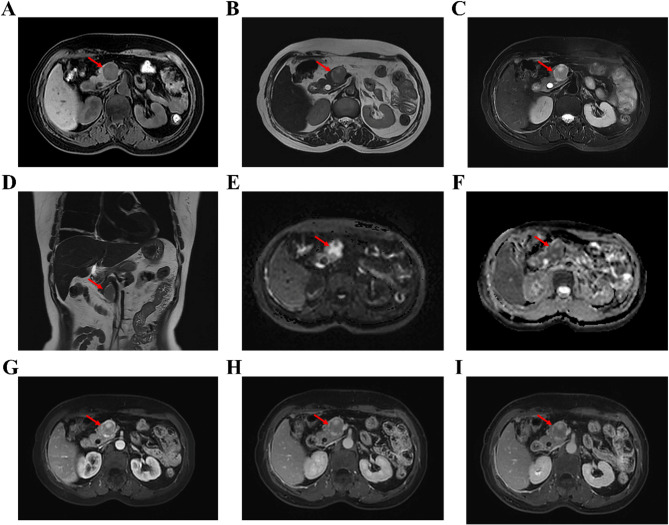

Case presentation: In February 2024, a woman in her 50s was admitted to the hospital with subxiphoid discomfort. Magnetic resonance imaging (MRI) of the upper abdomen revealed a round, solid mass in the pancreatic uncinate process. The patient underwent pancreatic mass resection and pancreaticojejunostomy, and the diagnosis of pancreatic PEComa was confirmed through pathological examination.

Conclusions: Imaging examinations appear valuable for a tentative diagnosis of pancreatic PEComa. Key imaging features include its frequent occurrence in the pancreatic head, typically small to moderate size, "pushing" as opposed to infiltrative growth pattern with well-defined margins, and the presence of a capsule. The lesions are usually solid and often exhibit mild to moderate heterogenous enhancement during the arterial phase, with reduced enhancement in the portal and delayed phases.